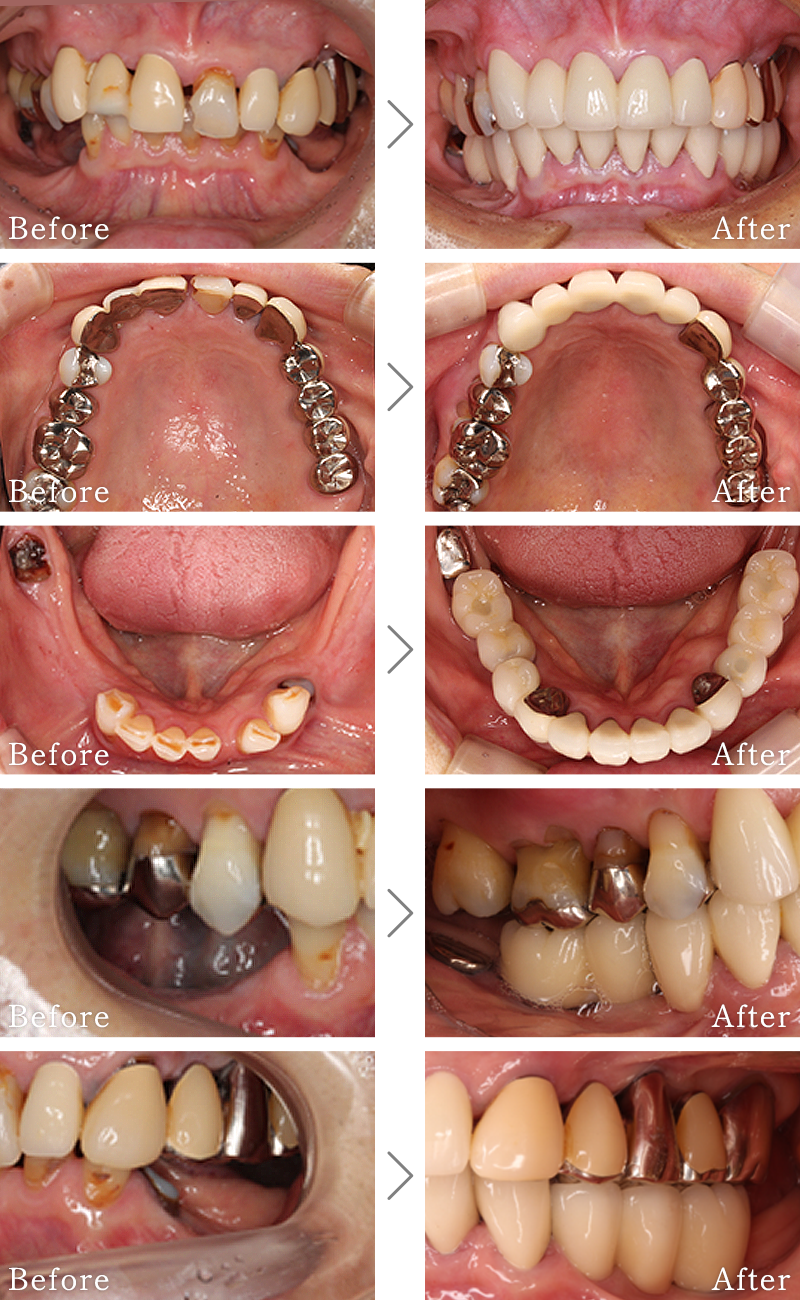

CASE4

主訴 右の奥歯は無くなって食事が噛めない。

治療法 上下2本ずつインプラントを使用して噛み合わせを回復させています。

治療期間 4ヶ月

費用 CT:16,500円(税込)

+ 静脈内鎮静法:66,000円(税込)

+ インプラント治療:2,103,200円(税込)

合計:2,185,700円(税込)

副作用

• 歯周病に感染・発症し重度に進行するとインプラントが抜けてしまうことがあります。

• 手術後は数日間腫れが出る場合があります。

CASE5

主訴 前歯がグラグラして噛めないのと抜けそうで心配。

治療法 抜歯した後、歯周病で溶けて無くなってしまった骨を再生する手術とインプラント手術を同時に行なっています。

治療期間 8ヶ月

+ インプラント治療:525,800円(税込)

+ 造骨処置:88,000円(税込)

合計:630,300円(税込)

• 造骨処置を行なった部分に内出血などがあらわれる場合があります。

CASE6

主訴 入れ歯が合わず、痛くて噛めない。食事ができない。

治療法 入れ歯を新しく作成し、噛み合わせなどの確認をしたのち、左右2本ずつインプラントを使用して噛める状態に回復させています。

治療期間 5ヶ月

+ インプラント治療:2,321,000円(税込)

合計:2,403,500円(税込)